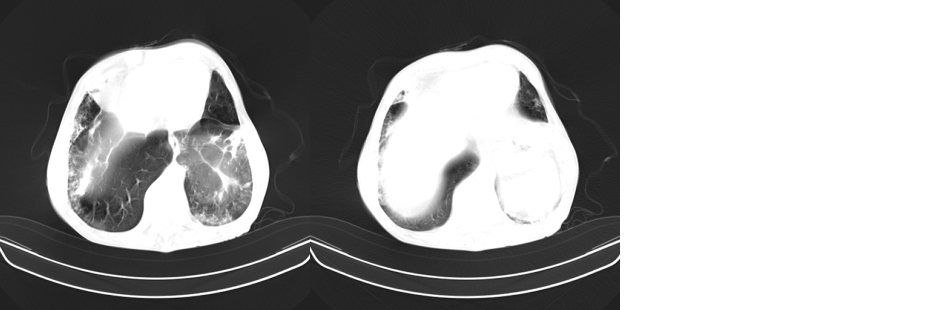

以下是引用mzh123在2007-8-26 19:58:00的发言:[br]两肺弥漫性斑片改变,其中可见大小不等之不规则空洞,结合既往病史还是考虑结核复发及感染。

以下是引用云翔在2007-8-26 20:54:00的发言:[br]这是44岁的肺吗?是否有先天病的基础?干酪性肺炎?